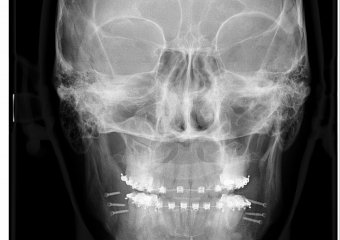

Telerradiografia frontal após cirurgia realizada em 2015 - Clínica Cliniface

Telerradiografia frontal após cirurgia realizada em 2015